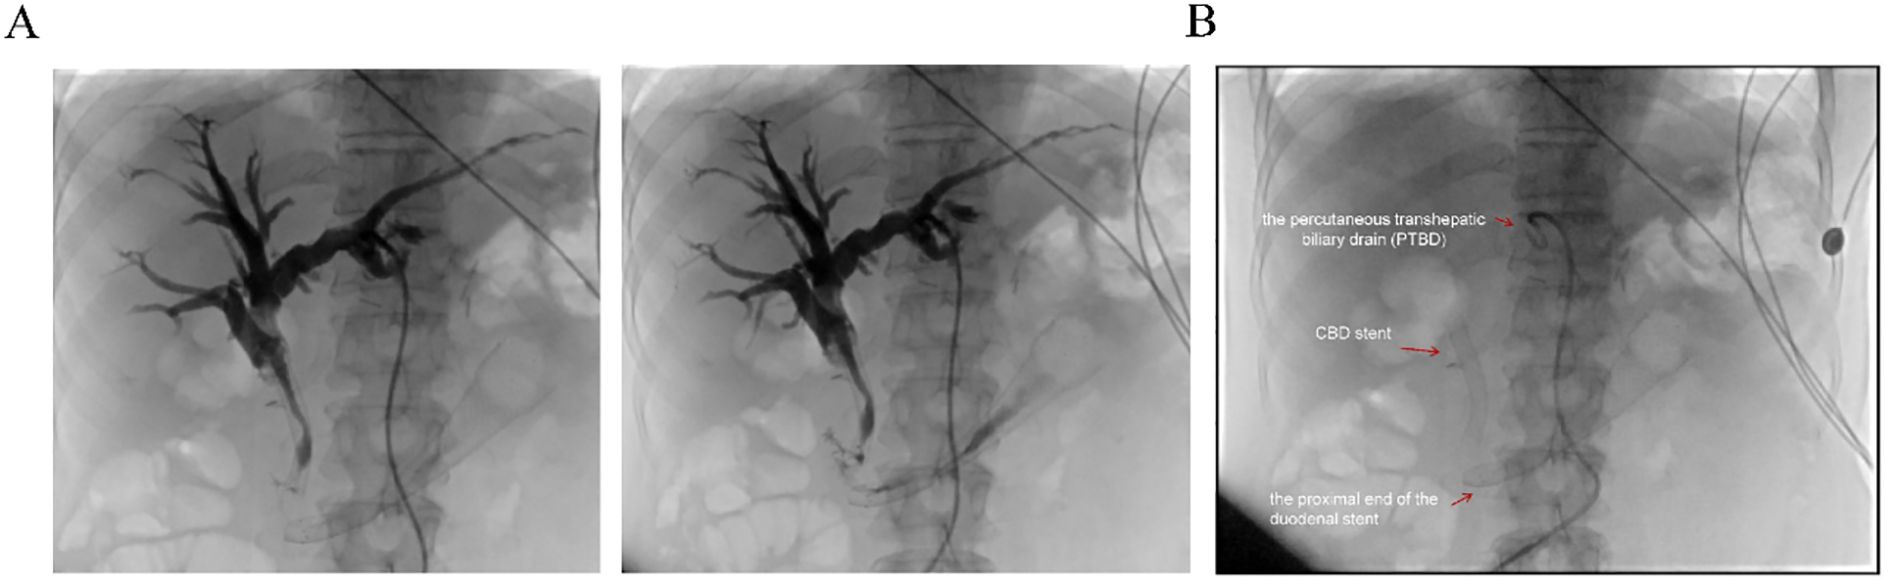

Biochemical improvement was observed within four days post-procedure: total bilirubin decreased from 80.8 μmol/L to 68.3 μmol/L, direct bilirubin from 41.4 μmol/L to 33.9 μmol/L, and γ-glutamyltransferase (GGT) from 783 U/L to 377 U/L. Percutaneous transhepatic cholangiography showed resolution of obstruction in both the intrahepatic bile ducts and the afferent loop (Figure 4A). Follow-up EGD one week later was performed to assess stent positioning and duodenal lumen patency, and confirmed optimal stent placement with no evidence of migration or recurrent obstruction (Figure 4B). the patient’s clinical condition and quality of life improved significantly.

Panel A shows two X-ray images of the biliary tree with visible branches. Panel B displays an annotated X-ray image indicating a percutaneous transhepatic biliary drain, common bile duct stent, and duodenal stent.

Figure 4. Postoperative imaging evaluation. (A) Post-stent placement percutaneous transhepatic cholangiography showing resolution of obstruction in both the intrahepatic bile ducts and the afferent loop. (B) Fluoroscopic view post-surgery demonstrating the properly positioned stent, absence of obstruction, and the patient’s subsequent clinical improvement. Red arrows indicate the proximal end of the duodenal stent, the previously placed CBD stent, and the percutaneous transhepatic biliary drain (PTBD).